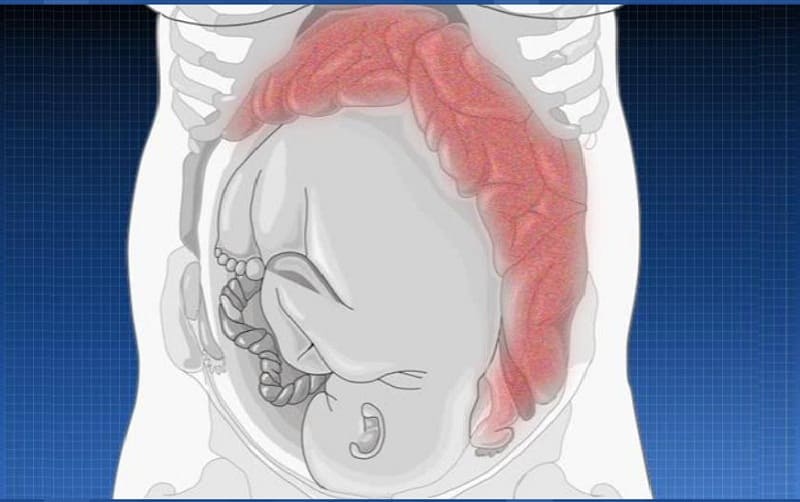

Заблуждения и факты о внутрибрюшной беременности